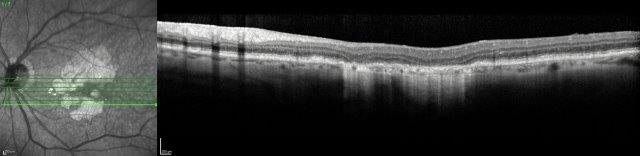

Several therapeutic approaches have been investigated for dry AMD and are in different stages of clinical trials, but as yet there is no agent that is shown to be a real ‘game-changer’ in management. One of the main goals is to find treatments that prevent or limit geographic atrophy (GA). This is the advanced stage of dry AMD characterised by loss of retinal photoreceptors, retinal epithelium and choriocapillaris. When seeing patients with dry AMD it is important to get good baseline data to characterise the extent of the disease and monitor progression, including autofluorescence photography and OCT scans (Figs 2 and 3).

Fig 2. A 72-year-old male’s atrophic AMD. Infrared and OCT images indicating cRORA.

Credit: Dr Oliver Comyn and the Christchurch Archer trial group

Some of the treatments under development include those targeting the complement pathway, senolytic therapy and gene therapy. Study results have been released for the complement inhibitor pegcetacoplan (Empaveli, Filly trial), which is administered by intravitreal injection and inhibits C3. This is the first study showing that GA progression can be slowed. However, the benefits of treatment compared to observation only became apparent after 18 months of monthly injections. Post-hoc analysis demonstrated reduction in progression from precursors of GA, or incomplete retinal pigment epithelium (RPE) and outer retinal atrophy (iRORA) to GA, also classified as complete outer RPE and outer retinal atrophy (cRORA)14. Overall, 81% of sham eyes showed progression from iRORA to cRORA, compared with 50% in the monthly pegcetacoplan group. There have been some significant adverse effects reported, including occlusive retinal vasculitis and non-arteritic ischaemic optic neuropathy. These reports are recent and under urgent review15.